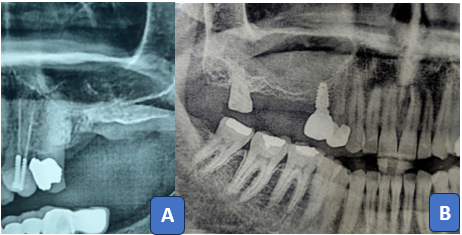

The Thin Wall Technique involves creating a thin lateral wall of the maxillary sinus before bone osteotomy, utilizing special tools to achieve optimal results. Preoperative radiograph was taken to evaluate the sinus condition (figure1)

Figure 1: Preoperative orthopantomograms of two patients (A&B) demonstrate insufficient bone height beneath the maxillary sinus due to pneumatization